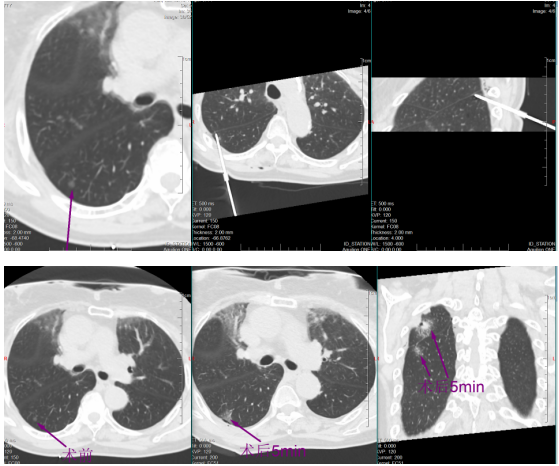

稍后,于明川与冯文汉等团队成员密切配合,向难度更高的第二枚结节发起冲击。这枚结节藏在叶间裂与胸膜构成的狭小夹角内,可操作空间极小,如同在“夹缝中绣花”。按照术前预案,于明川放弃平行进针思路,采用由下而上的特殊进针方式,巧妙避开关键解剖结构。针尖精准抵达结节区域,经过反复测量确认安全后,30瓦功率持续消融一分钟。术中,黄女士的心率、血压始终平稳,未出现任何不良反应。术后CT扫描证实,结节被完全覆盖,烧灼区与叶间裂仅隔几毫米,这毫厘之间的精准,正是生命安全的坚实屏障。

一小时后,铅门再次打开。于明川将黄女士的儿女引至屏幕前,影像清晰地显示:两枚结节已被完全覆盖,消融范围边缘距离关键解剖结构仅存毫厘之差。“两个结节都顺利消融成功了,没有并发症,手术很成功!” 话音落下,黄女士儿女心中悬了许久的大石终于落地。看着术后安然躺在病床上、面容平和的母亲,他们眼中盈满欣慰。